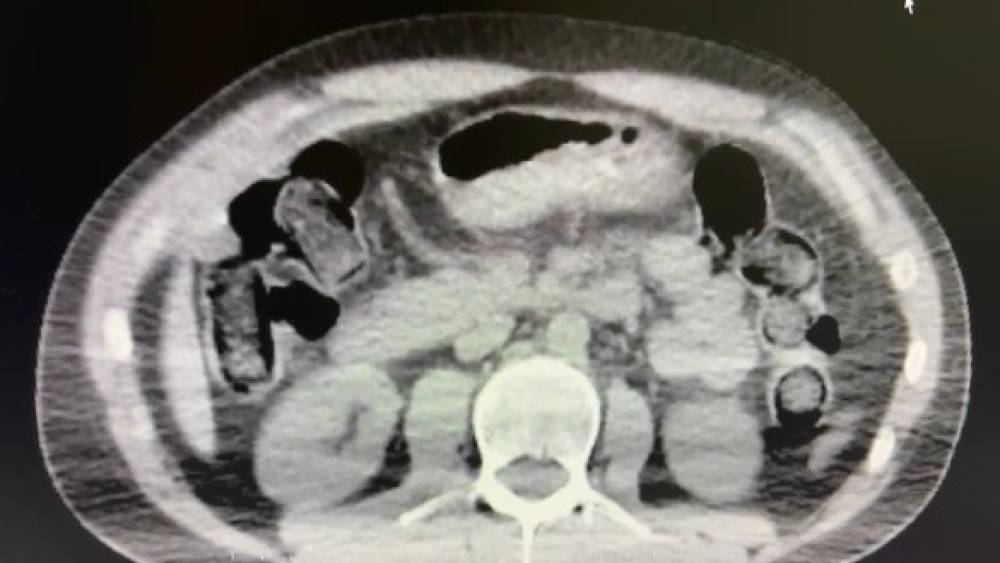

Nevşehir’de polis ekiplerince düzenlenen operasyonda midelerinde uyuşturucu sevkiyatı yapan 2 şüpheli gözaltına alındı.Nevşehir İl Emniyet Müdürlüğü Narkotik Suçlarla Mücadele Şube Müdürlüğü ekipleri, kentte uyuşturucu ve uyarıcı madde ticareti yapmak ve kullanmak suretiyle vatandaşları zehirleyen sokak satıcılarına yönelik çalışma başlattı. Cumhuriyet Başsavcılığı koordinesinde çalışmalarını yoğunlaştıran ekipler, şüpheliler S.B. ve O.R.’nin ’yutma yöntemi’ ile kente uyuşturucu madde sevk edeceği bilgisi üzerine operasyon düzenledi. Şüphelilerin ikametlerinde ve araçlarında yapılan aramada 101 kapsül halinde 722 gram uyuşturucu madde, 1 adet hassas terazi, uyuşturucu madde sevkiyatında yutma yönteminde kullanılan muhtelif materyaller, uyuşturucu madde ticaretinden elde edilen 20 bin 210 TL, bin 320 euro ve 10 ABD doları ele geçirildi. Emniyetteki işlemlerinin ardından adliyeye sevk edilen 2 şüpheli, çıkarıldıkları mahkemece tutuklanarak cezaevine gönderildi.

Nevşehir İl Emniyet Müdürlüğü Narkotik Suçlarla Mücadele Şube Müdürlüğü ekipleri, kentte uyuşturucu ve uyarıcı madde ticareti yapmak ve kullanmak suretiyle vatandaşları zehirleyen sokak satıcılarına yönelik çalışma başlattı. Cumhuriyet Başsavcılığı koordinesinde çalışmalarını yoğunlaştıran ekipler, şüpheliler S.B. ve O.R.’nin ’yutma yöntemi’ ile kente uyuşturucu madde sevk edeceği bilgisi üzerine operasyon düzenledi. Şüphelilerin ikametlerinde ve araçlarında yapılan aramada 101 kapsül halinde 722 gram uyuşturucu madde, 1 adet hassas terazi, uyuşturucu madde sevkiyatında yutma yönteminde kullanılan muhtelif materyaller, uyuşturucu madde ticaretinden elde edilen 20 bin 210 TL, bin 320 euro ve 10 ABD doları ele geçirildi. Emniyetteki işlemlerinin ardından adliyeye sevk edilen 2 şüpheli, çıkarıldıkları mahkemece tutuklanarak cezaevine gönderildi.